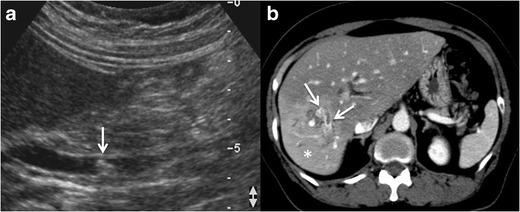

Radiologists seldom encounter parasitic diseases in their daily practice in most of Europe, although the incidence of these diseases is increasing due to migration and tourism from/to endemic areas. Moreover, some parasitic diseases are still endemic in certain European regions, and immunocompromised individuals also pose a higher risk of developing these conditions. This article reviews and summarises the imaging findings of some of the most important and frequent human parasitic diseases, including information about the parasite's life cycle, pathophysiology, clinical findings, diagnosis, and treatment. We include malaria, amoebiasis, toxoplasmosis, trypanosomiasis, leishmaniasis, echinococcosis, cysticercosis, clonorchiasis, schistosomiasis, fascioliasis, ascariasis, anisakiasis, dracunculiasis, and strongyloidiasis. The aim of this review is to help radiologists when dealing with these diseases or in cases where they are suspected. Teaching Points • Incidence of parasitic diseases is increasing due to migratory movements and travelling. • Some parasitic diseases are still endemic in certain regions in Europe. • Parasitic diseases can have complex life cycles often involving different hosts. • Prompt diagnosis and treatment is essential for patient management in parasitic diseases. • Radiologists should be able to recognise and suspect the most relevant parasitic diseases.

在欧洲大部分地区,放射科医生在日常工作中很少遇到寄生虫病,尽管由于往返于流行地区的移民和旅游活动,这些疾病的发病率正在上升。此外,某些寄生虫病在欧洲的某些地区仍然流行,免疫功能低下的个体感染这些疾病的风险也更高。本文回顾并总结了一些最重要且常见的人类寄生虫病的影像学表现,包括有关寄生虫生命周期、病理生理学、临床表现、诊断和治疗的信息。我们涵盖了疟疾、阿米巴病、弓形虫病、锥虫病、利什曼病、棘球蚴病、囊尾蚴病、华支睾吸虫病、血吸虫病、片形吸虫病、蛔虫病、异尖线虫病、麦地那龙线虫病和粪类圆线虫病。这篇综述的目的是在放射科医生处理这些疾病或怀疑患有这些疾病的病例时提供帮助。教学要点 • 由于人口迁移和旅行,寄生虫病的发病率正在上升。 • 某些寄生虫病在欧洲的某些地区仍然流行。 • 寄生虫病可能具有复杂的生命周期,通常涉及不同的宿主。 • 及时诊断和治疗对于寄生虫病患者的管理至关重要。 • 放射科医生应该能够识别和怀疑最相关的寄生虫病。